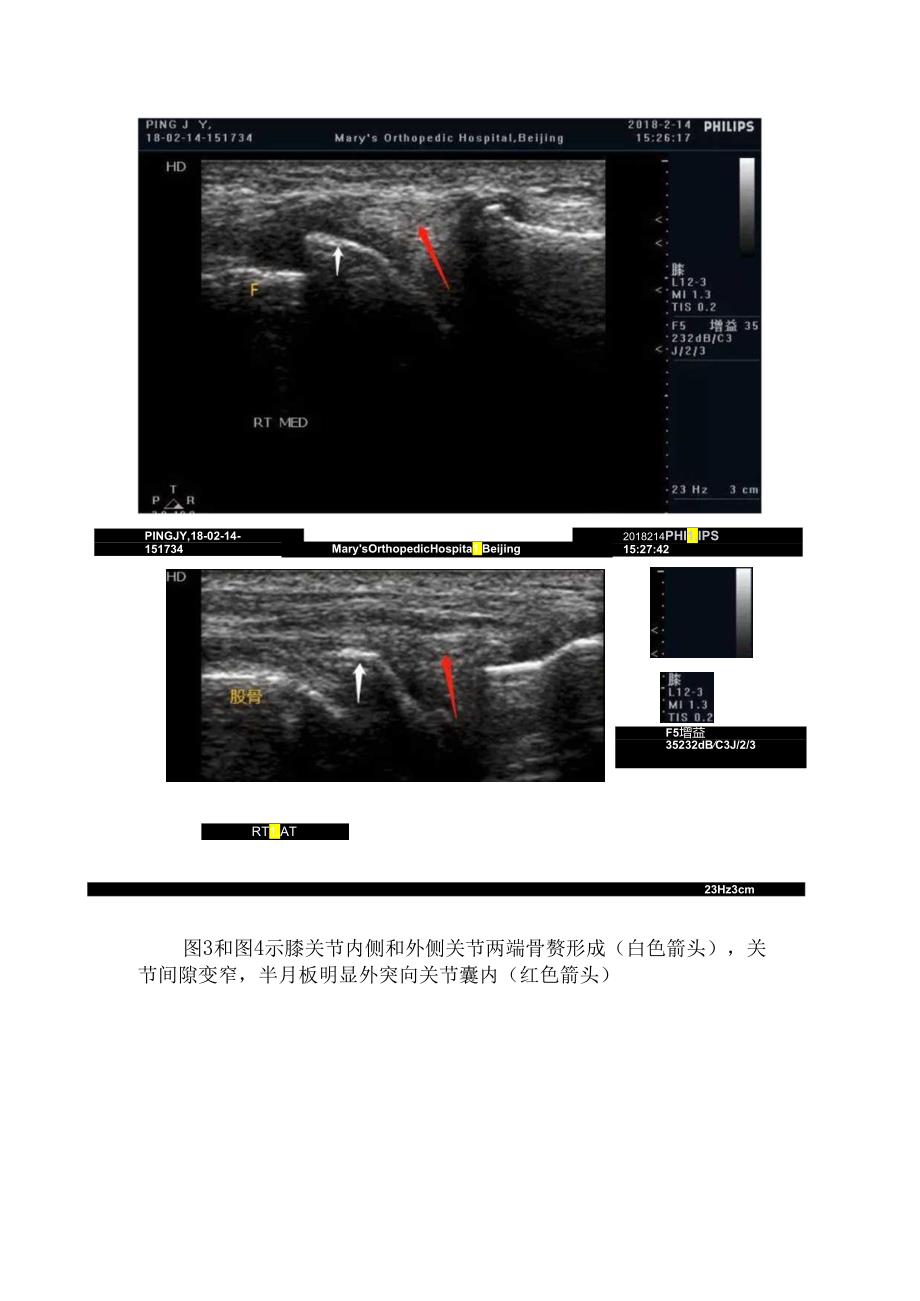

2、。内侧区:主要包括膝内侧副韧带,内侧半月板和鹅足腱止点等。内侧半月板位于股骨与胫骨之间,因其为纤维软骨,超声上正常呈高回声,纵切面上呈三角形,尖部指向关节内。外侧区:包括膝外侧副韧带和外侧半月板。膝后区:除胴动脉、胴静脉和胫神经外,还应重点注意腓肠肌内侧头-半膜肌腱滑囊,正常情况下,该滑囊仅有少量滑液,滑囊异常扩张时,形成Baker囊肿。病例分享老年女性患者,主诉双侧膝关节肿胀、疼痛并活动障碍。临床怀疑骨性关节炎。超声检查所见如下:图I修上囊扩张,见较大量无回声液体(F),滑膜增生(箭头示)图2版上囊内骨化的关节游离体,后方伴声影PINGJY,18-02-14-1517342018214PHI

3、1.IPS15:27:42MarysOrthopedicHospita1.BeijingF5增益35232dBC3J/2/3RT1.AT23Hz3cm图3和图4示膝关节内侧和外侧关节两端骨赘形成(白色箭头),关节间隙变窄,半月板明显外突向关节囊内(红色箭头)ZHAOBS,1812-06-1131232018-12-6PHI1.IPS11:35:49MarysOrthopedicHospitaIfBeijingH5增益40-232dBC3J/2/311Hz4cm图5股骨关节透明软骨变薄(箭头示),厚度不均匀PlNGJY,18021A1517342018-2-14PHI1.IPS15:26:53M